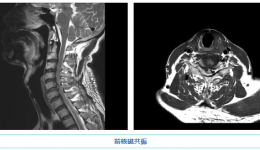

• 看茂医丨显微镜下颈椎微创手术助两高风险患者重获新生

看茂医丨显微镜下颈椎微创手术助两高风险患者重获新生

近日,茂名市人民医院脊柱外科二区赵斌修团队凭借精湛的技艺于同一日为两名严重的颈椎病患者成功实施了情况复杂、风险程度极高的颈椎前路减压植骨融合内固定微创手术。据了解,两名患者均为患病多年且在近期病情急剧变化、情况急转之下,脊柱外科二...